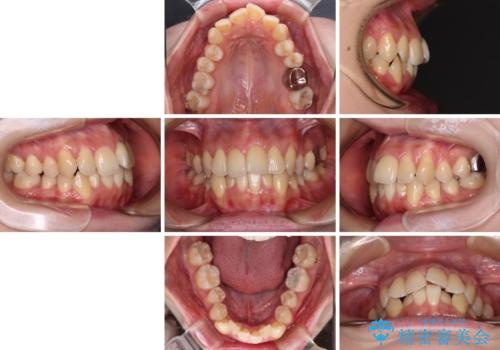

【モニター】急速拡大装置 狭い歯列を拡大してワイヤー装置で短期間治療

1. 開始前

2. 治療途中

3. 終了時